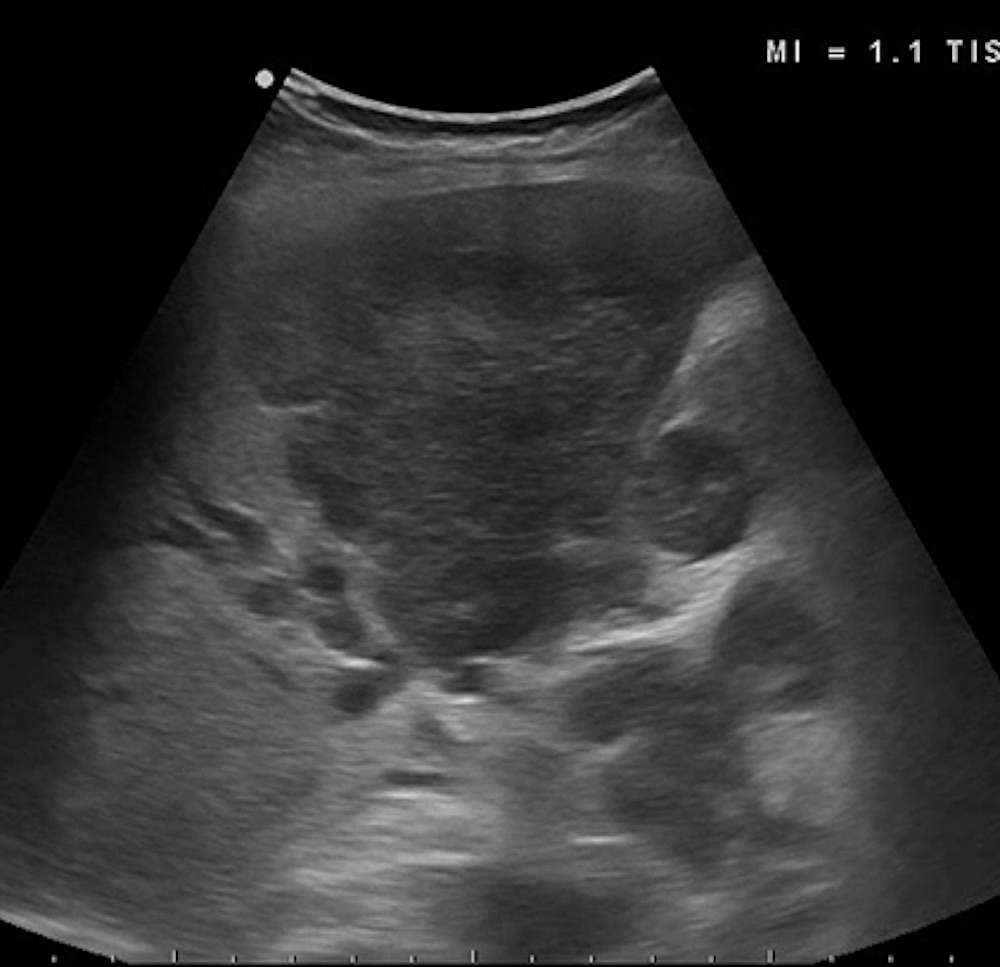

Mass lesions typically appear as heterogeneous or hypoechoic areas (Figure 3), while hepatic steatosis causes increased echogenicity of the parenchyma (Figure 4).